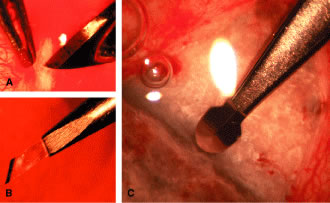

irrigated away, and chamber deepening cannot readily be performed.  Fig. 10. Peripheral iridectomy with the use of a preplaced suture to retract the

edges of the incision. A. An incision is made through two thirds of the thickness of the sclera

directly at the corneoscleral sulcus. B. A 9-0 white virgin silk suture is placed so that it will be able to be

retracted from the depths of the incision. C. The suture is looped and used to retract the edges of the incision superiorly

and inferiorly. The incision is completed, permitting prolapse

of a small knuckle of iris. D. The iris is grasped with a fine-toothed forceps. E. The iris is pulled over the blade of the DeWecker scissors; after the

position of the iris is noted, the blades are closed and the tissue is

excised. F. The tip of an irrigator is placed just inside the incision, with care

taken to ensure that it does not enter the anterior chamber. Remnants

of the pigment epithelium are flushed away, and the iris is permitted

to return to its proper position so that the pupil is completely round. (Spaeth GL. Glaucoma surgery. In Spaeth GL (ed). Ophthalmic Surgery: Principles

and Practice. Philadelphia: WB Saunders, 1990.) Fig. 10. Peripheral iridectomy with the use of a preplaced suture to retract the

edges of the incision. A. An incision is made through two thirds of the thickness of the sclera

directly at the corneoscleral sulcus. B. A 9-0 white virgin silk suture is placed so that it will be able to be

retracted from the depths of the incision. C. The suture is looped and used to retract the edges of the incision superiorly

and inferiorly. The incision is completed, permitting prolapse

of a small knuckle of iris. D. The iris is grasped with a fine-toothed forceps. E. The iris is pulled over the blade of the DeWecker scissors; after the

position of the iris is noted, the blades are closed and the tissue is

excised. F. The tip of an irrigator is placed just inside the incision, with care

taken to ensure that it does not enter the anterior chamber. Remnants

of the pigment epithelium are flushed away, and the iris is permitted

to return to its proper position so that the pupil is completely round. (Spaeth GL. Glaucoma surgery. In Spaeth GL (ed). Ophthalmic Surgery: Principles

and Practice. Philadelphia: WB Saunders, 1990.)

To prevent the tip of the knife used to develop the corneoscleral incision

from damaging the iris or lens, it is preferable to use a broad blade, such

as the no. 67 Beaver blade. Multiple small scratches are made, with

the surgeon verifying that the depth of the incision is uniform

from end to end. Some surgeons prefer an anteriorly shelved incision

because it tends to close more easily; in the past, many surgeons did

not place a suture through this type of incision. However, a perpendicular

incision allows the iris to prolapse more readily, gives better

visualization, and facilitates the procedure. The availability of fine

suture material allows tight closure of the incision with minimal irritation

or difficulty. The scissors used to perform the iridectomy should

be sharp and should be tested immediately before the procedure to

ensure their proper operating condition. We prefer the use of a preplaced suture, as seen in Figure 10. This approach provides a clearer view of the process of creating the

corneal incision, it aids in prolapsing the iris, and it allows for immediate

closure with a suture that the surgeon knows is perfectly placed. Any

of a number of sutures is satisfactory. Absorbable polyglactin [Vicryl (Ethicon, Somerville, NJ)] works well and has the advantage

of not requiring removal. A 9-0 nylon suture also is satisfactory; it

is thick enough to be used to retract the tissue yet fine enough

to be well tolerated. The small fornix-based flap can be closed by stretching it toward one side, especially

if a radial relaxing incision approximately 2 mm long

and extending from the limbus has been performed (Fig. 11). This closure can be done with the same suture used to close the corneoscleral